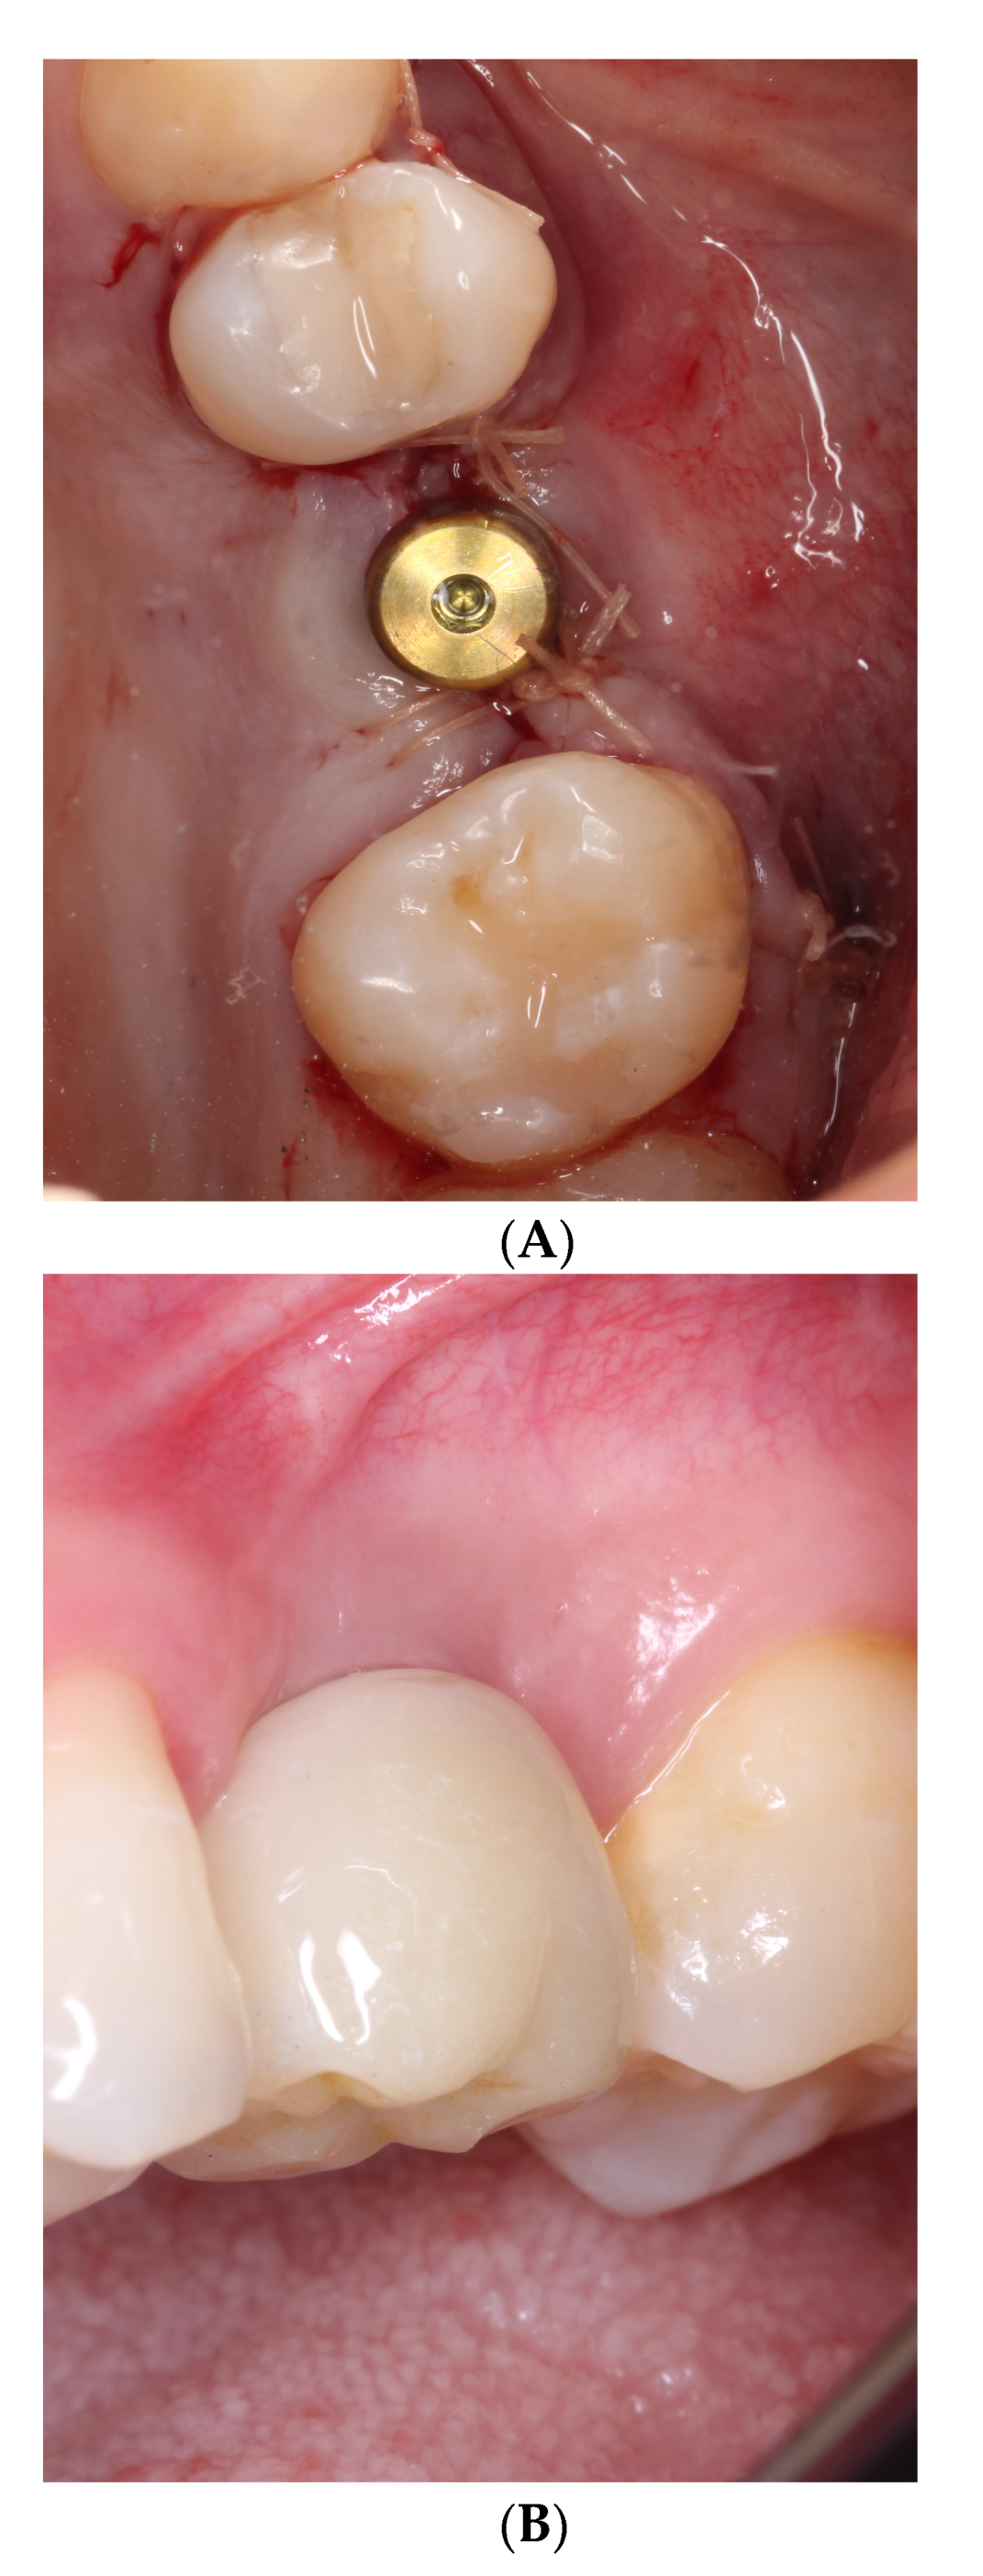

2.2. Surgical Procedures

2.3. Prosthetic Procedures